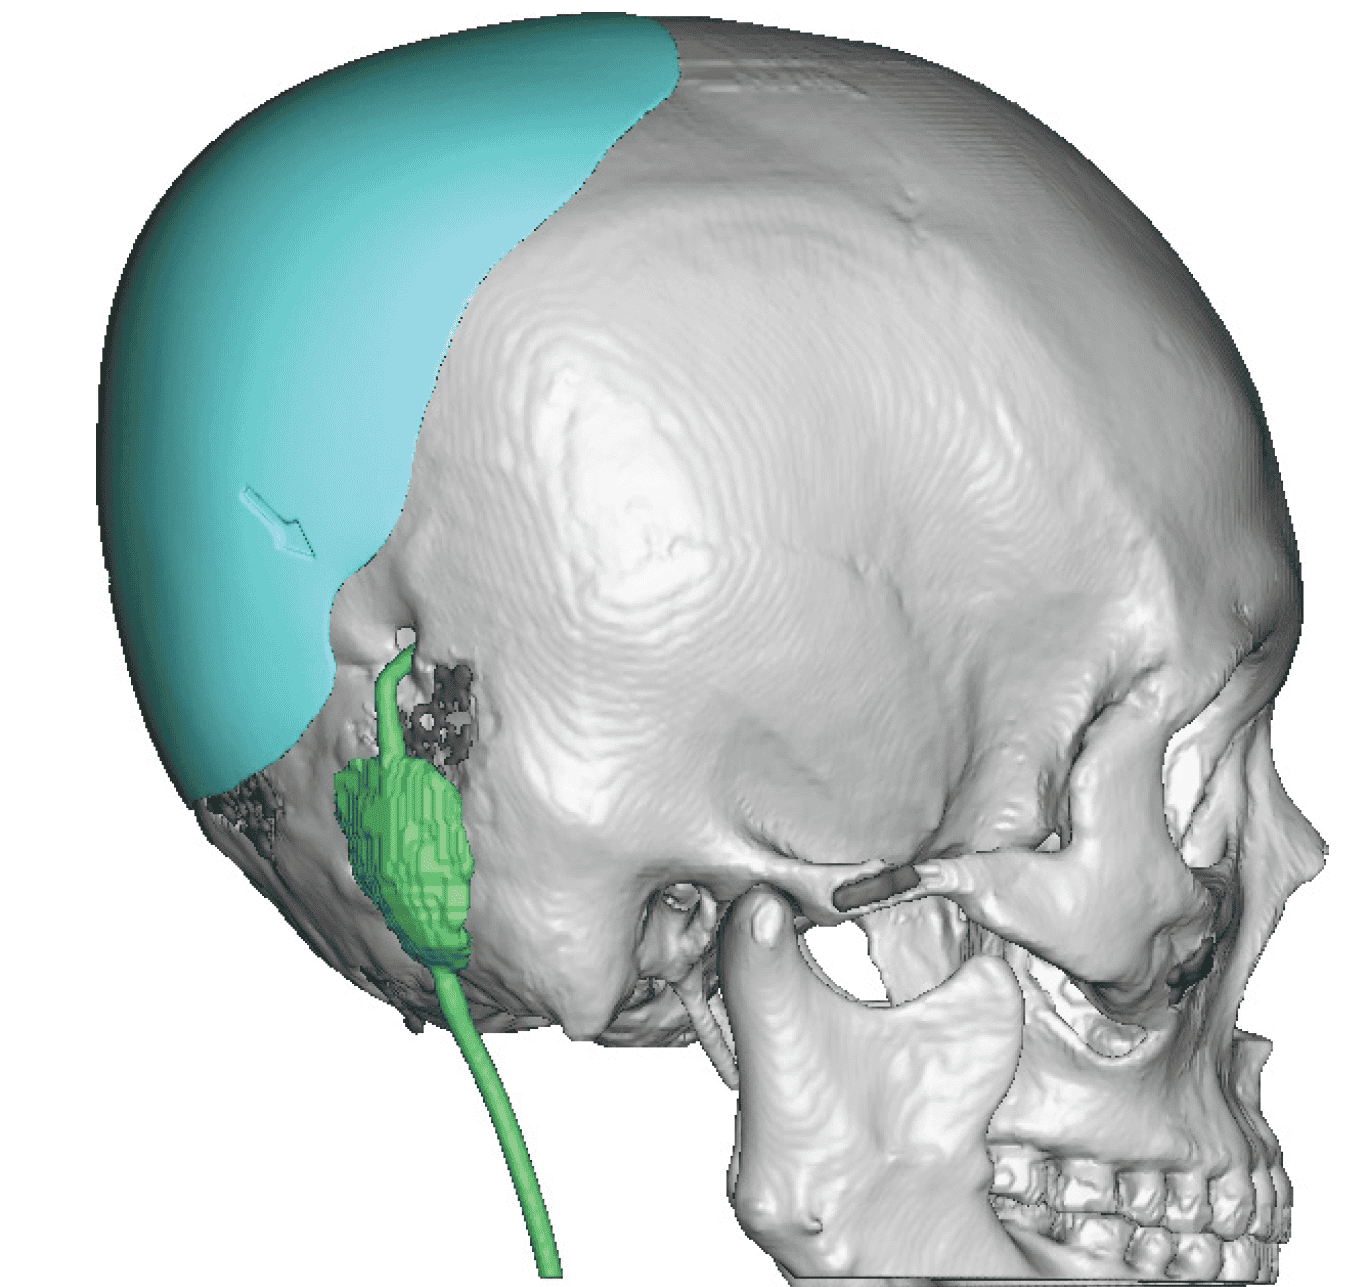

Desire for head shape asymmetry improvement as the final stage of total skull reshaping surgeries. (previous skull implants are in green color)

Placement of custom temporal implant through an incision behind the ear.

Desire for head shape asymmetry improvement as the final stage of total skull reshaping surgeries. (previous skull implants are in green color)

Placement of custom temporal implant through an incision behind the ear.